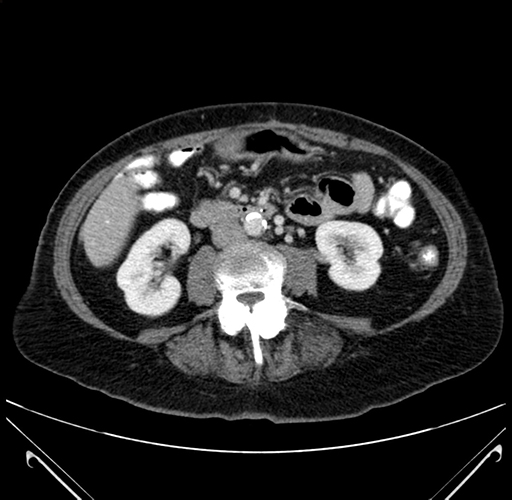

Pre-Chemo: Axial Venous

Axial Venous